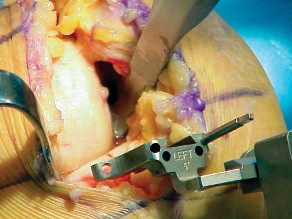

2. الوضع الجراحي والتعرض

- الوضع: يُوضع المريض في وضع الاستلقاء (Supine positioning) مع وضع كيس رمل أسفل الركبة أو حامل للساق يسمح بثني وفرد الركبة. يجب أن يكون الوضع مماثلاً لوضع جراحة TKA، مع استعداد لتحويل الإجراء إلى TKA إذا لزم الأمر.

- العاصبة (Tourniquet): تُستخدم عاصبة وتُوضع في أعلى الفخذ لتقليل النزيف.

-

الشق الجراحي:

يُستخدم شق طولي في الجانب الإنسي (الداخلي) من الركبة. يجب أن يكون الشق كبيرًا بما يكفي لتوفير رؤية جيدة للمفصل الرضفي الفخذي وإمكانية التحويل إلى TKA.

- فتح المفصل (Arthrotomy): يكون الفتح خطيًا وموازياً لألياف الوتر الرضفي، ويمتد إلى عظم الظنبوب وإلى الجزء السفلي من الرضفة.

- تحرير الأنسجة الرخوة: يتم قطع الغضروف الهلالي لتحرير الأنسجة الرخوة من عظم الظنبوب، ويتم تطوير سديلة تحت السمحاق في نمط دائري حول الظنبوب. يُمدد هذا التحرير خلفيًا لضمان توازن الأربطة.

-

تصحيح التشوه:

الهدف هو تحقيق تصحيح طفيف للتشوه، مع وجود رخاوة كاذبة طفيفة عند تطبيق ضغط تفحجي في نهاية الإجراء. يجب تجنب التصحيح المفرط.